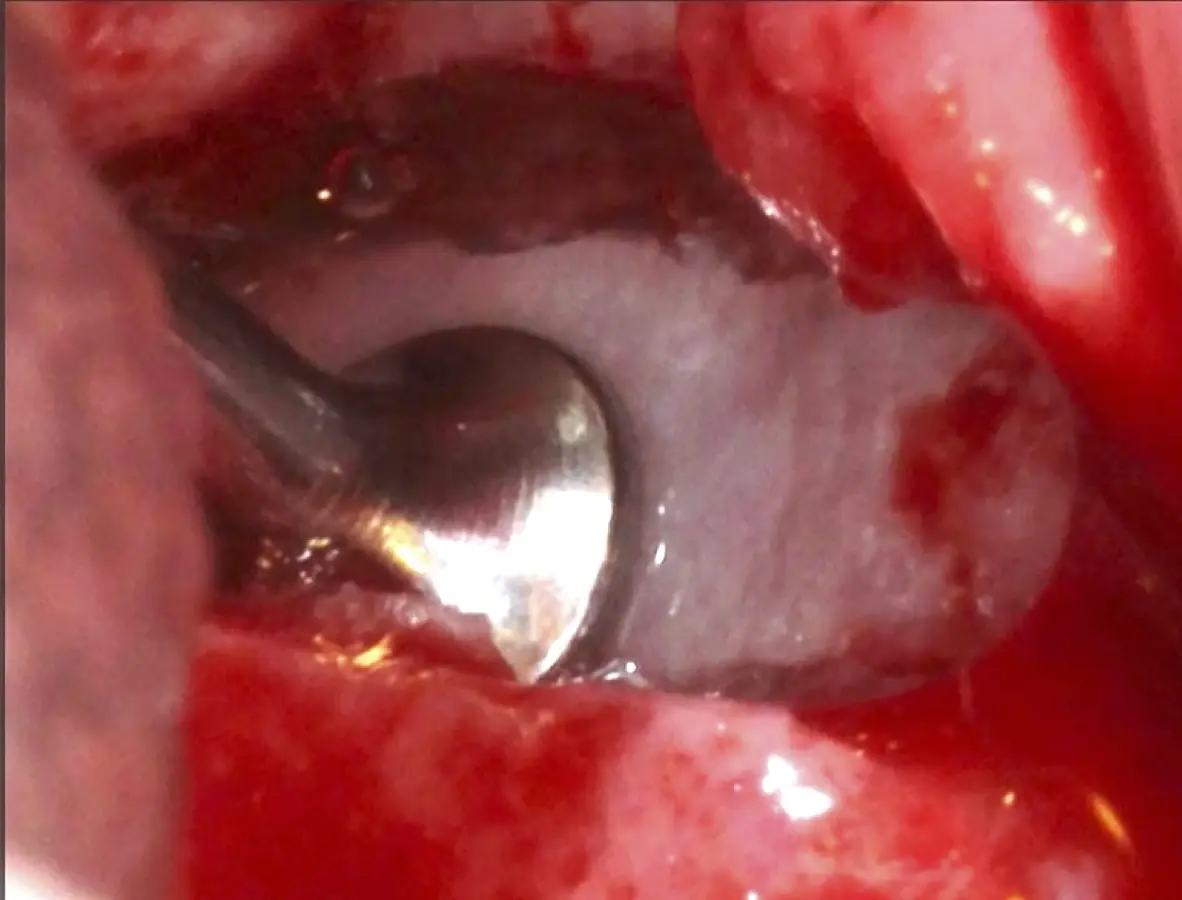

La técnica se inicia con la colocación de anestesia infiltrativa, posteriormente se realiza una incisión crestal o paracrestal con posibles liberantes verticales que deben de estar alejadas por lo menos 5 mm de los límites de la futura ventana y sobrepasar la línea mucogingival. Se realiza una elevación de colgajo, se inicia la antrostomía y antroplastía. Para ello, se emplea el inserto redondo diamantado de corte al momento de delimitar los bordes de la ventana de acceso. Luego se cambia al inserto aserrado liso de calibre fino con superficie diamantada, para profundizar y eliminar el hueso en el contorno de la ventana. Una vez que se traslucen los tejidos, se puede optar por el retiro de la tapa ósea o el levantamiento de ésta junto con la membrana.

Se inicia la elevación de la membrana de Schneider con el inserto redondeado no cortante en forma de disco, empleando movimientos suaves. El levantamiento puede complementarse con elevadores convencionales, siguiendo la dirección mesiodistal. La fase de desprendimiento inicia con el piso y sigue hacia la pared mesial para terminar, y de ser necesario, hacia la pared posterior. Existen diversos insertos con angulaciones y longitudes para mayor accesibilidad16 (Figura 1).